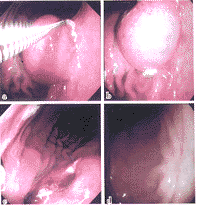

對於胃平滑肌瘤的診斷除臨床上出現上消化道出血、腹痛腹部包塊者應疑及該病外,主要依靠X線及胃鏡檢查。X線檢查可見孤立的圓形或橢圓形的充盈缺損腫瘤周圍黏膜正常。充盈缺損區有龕影提示平滑肌瘤有潰瘍腫瘤向胃外突出時可見胃壁畸形,或呈外在壓跡樣缺損胃鏡檢查可見半球形或球形隆起黏膜緊張光滑色澤正常頂部可有缺血壞死性潰瘍術前確診較困難常需要才能證實。

5.胃鏡檢查 普通內鏡可以直觀腔內型腫瘤的形態大小及生長特點,亦可直接行組織活檢以取得病理學證據,甚至可經胃鏡行胃平滑肌瘤摘除術但對於沒有侵犯黏膜的腫瘤及腔外型腫瘤則意義不大可見半球形或球形隆起,表面黏膜 緊張光滑,色澤與周圍黏膜相同,頂部有時可出現缺血壞死性潰瘍術前確診較困難,常需要組織學檢查才能證實。